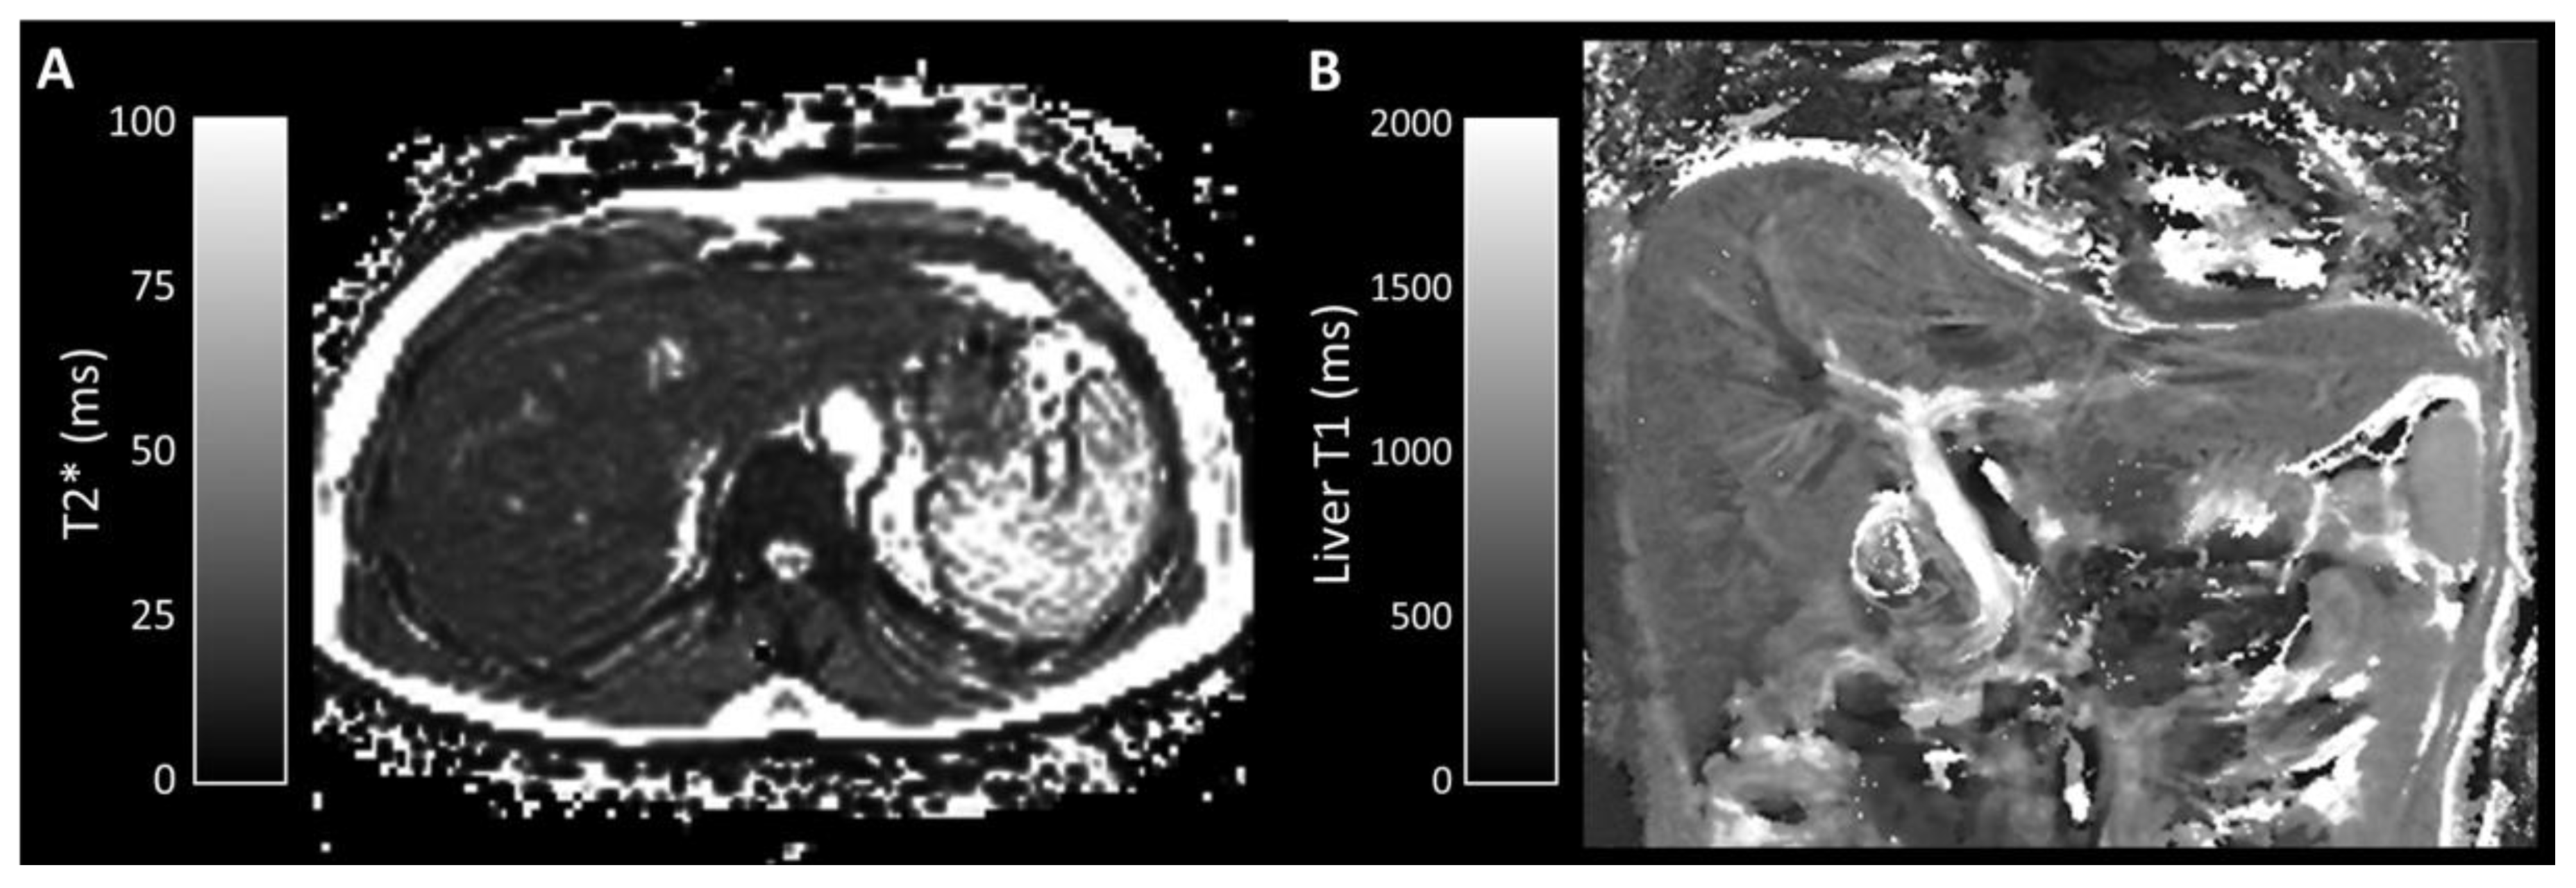

Appendix A.1.3. T1 Mapping

Appendix A.1.4. Phase-Contrast MRI

Appendix A.2.2. T1 Mapping

Appendix A.2.3. Phase-Contrast MRI

| Liver T1 (ms) | 715 (544–848) | 740 (594–919) | 0.873 |

| Portal venous flow (qPV) (mL/min/100 g) | 64.2 (45.6–137.6) | 56.2 (37.5–93.0) | 0.667 |

| Estimated Total Liver Blood Flow (eTLBF) (mL/min/100 g) | 91.8 (63.5–145.7) | 62.1 (27.9–119.3) | 0.151 |